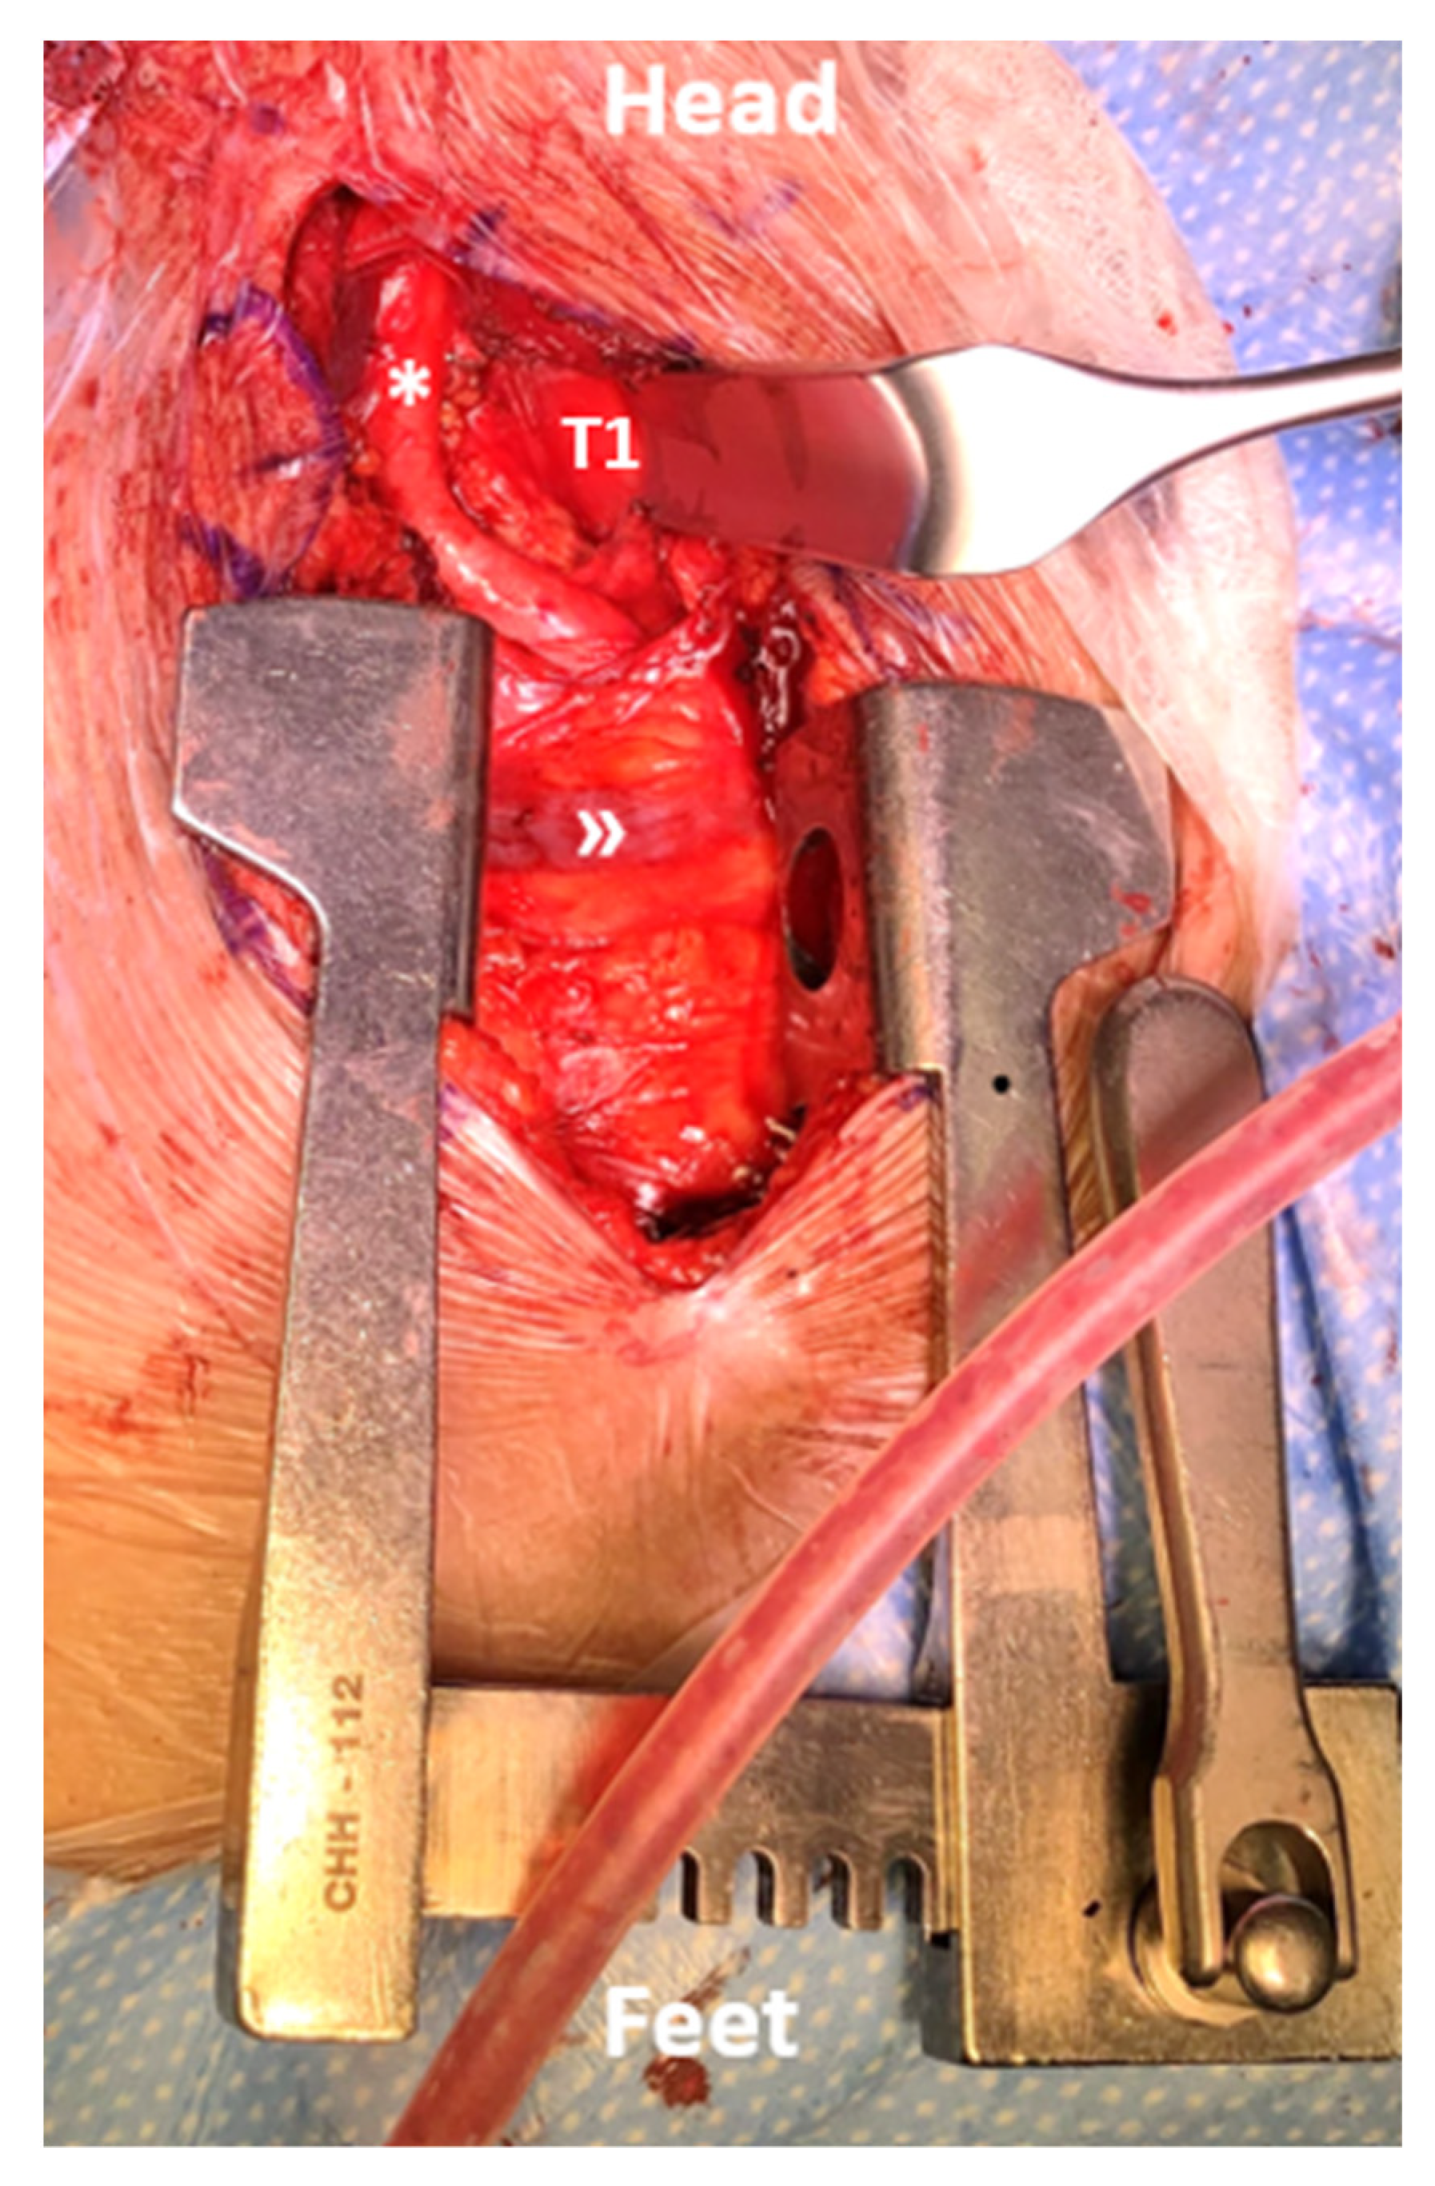

Figure 2.

Intraoperative view of the distraction phase and exposure of the mediastinum for an anterior T1 corpectomy. The proximal carotid artery (*) and brachiocephalic trunk (») are visualized boundaries of the approach.

In this area, with which the surgical specialists involved are usually not familiar, sharp transection is needed on the sterno-thyroid muscles for mobilization of the larynx medially and inter-fascial dissection is deepened to retract the carotid artery and jugular veins laterally. The course of the recurrent laryngeal nerve is carefully monitored at this point to prevent stretching injury. Depending on the segment addressed, ligation of thyroid vessels can additionally be required. Soft tissue retraction is achieved by common cervical retractors (Jarit, Integra, Princeton, NJ, USA), and the correct exposure is verified by a.p. and lateral fluoroscopy. Figure 2 illustrates the view of the anterior procedure of the approach.